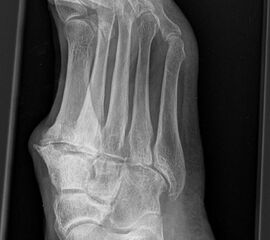

• konventionelle Röntgenbilder mit Belastung im Stehen a. p. und seitlich, ggf. schräg (Abb. 9, 10 und 11).

Es gibt neben der Möglichkeit mit der in situ TMT II, III Arthrodese auch die Möglichkeit Fehlstellungen wie den Pes metatarsus adductus zu adressieren (Abb. 9 und Abb. 24 zeigen das prä- und postoperative Röntgenbild eines Patienten mit Pes adductus Korrektur).